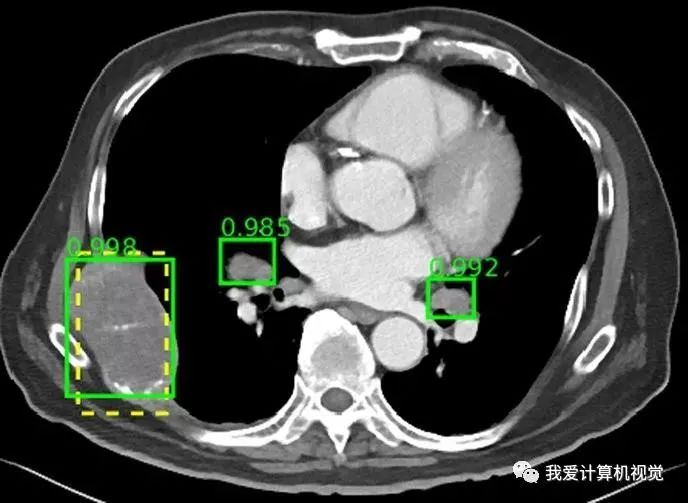

整个数据库图像病变类型包括肾脏病变,骨病变,肺结节和淋巴结肿大。包含来自 10,000 多个病例研究的超过 32,000 个病变标注,是目前面向所有人可公开获得的最大的医学图像数据集。